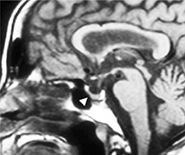

図1の矢頭の先の脳の底のほぼ中央に脳からぶら下がっている径1 cmほどの円い組織が下垂体です。そしてホルモンと呼ばれる様々な物質を作って体の状態を調節しています。

脳にできる腫瘍の内、約20%が図2のように下垂体にできます。そのほぼ99%が良性であり、ホルモンを作っているものと作っていないものがあります。およそ半数がホルモンを作っておらず、頭痛などの症状で検査して偶然見つかる場合や腫瘍が大きくなって下垂体のすぐ上にある目の神経を圧迫して目が見えづらくなって見つかります。一方、腫瘍がホルモンを作っている場合は、ホルモンの働きが強くなって様々な症状がでます。例えば成長ホルモンが作られ過ぎると、指の節々が太くなったり、眉毛や顎の部分の骨が出っ張ってきたりして先端肥大症という状態になります。また甲状腺や副腎を刺激するホルモンが作られ過ぎると、甲状腺機能亢進症(バセドー病)による動悸や発汗、副腎機能亢進症による肥満や倦怠感がおこります。

下垂体腫瘍の治療法としては、薬物によって腫瘍の縮小やホルモンの調節を行う内科的治療と、手術により取り除いてしまう外科的治療があります。残念ながら薬物による腫瘍の縮小が期待できるものは、現時点ではまだ成長ホルモンとプロラクチンを作っている腫瘍のみです。その他の腫瘍の場合や薬物の効果が不十分な場合などは外科的手術が必要になります。幸いにも他の脳腫瘍とは異なり、下垂体腫瘍は頭蓋骨の一部を切りとることなく、図2の矢印の方向に鼻の穴を経由して行う方法が一般的です。ただ、手術用顕微鏡を使用していた時代は鼻の穴を経由するためその視野は狭くて約1.5 cmほどしかなく、完全に取り除けない場合もありました。しかし、当科では平成23年7月より神経内視鏡を使用するようになり、図2の矢印の部分までそれを挿入することで、顕微鏡より明るく広い視野で手術ができるようになりました。その結果、径が2.5cm以上の腫瘍の摘出率が改善しました。図3は図2の手術後のMRIで、腫瘍が完全に取り除かれています。また、この方法ですと手術時間も3時間程度で出血量も少なく、患者さんの術後の負担は頭蓋骨を取り除く場合より格段に軽く、翌日から歩いたり食事を摂ったりすることも可能です。手術により起こりうる合併症は、正常の下垂体の機能が低下したり、尿量が増えたりすることです。そのため、一次的にはそれらを調節するホルモンの補充が必要になる場合もありますが、大部分は一次的なもので数週から数ヶ月で回復することがほとんどです。

図1

図2